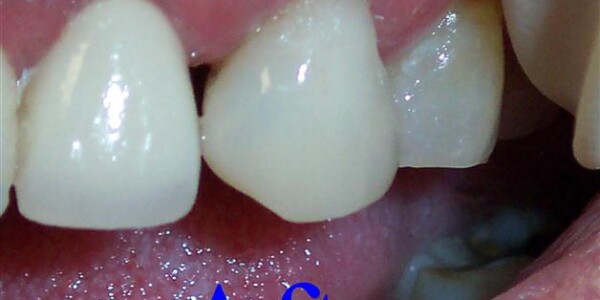

Restorative Dentistry

Restorative dentistry services focus on repairing teeth damaged to cavities, tooth decay, or trauma. From our beginning, it has been our goal to help our patients restore strength and structure to their smiles. We are committed to helping your smile stay beautiful and healthy for a lifetime. We incorporate the latest dental technology to ensure you receive the most advanced care. Our restorative services include:

Crowns